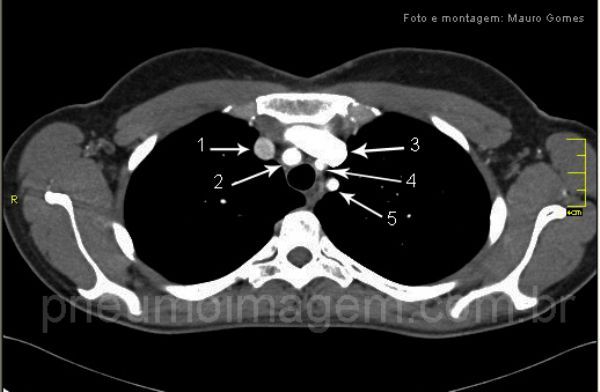

De25-10-2010S1I28.jpg)

Anatomia vascular.

(1) veia braquicefálica direita;

(2) artéria braquicefálica;

(3) artéria carótida esquerda;

(4) artéria subclávia esquerda.

Na direção da seta amarela, o timo normal.

Chaves: vasos normais;

(1) the right brachiocephalic vein,

(2) brachiocephalic artery,

(3) the left carotid artery,

(4) the left subclavian artery;normal thymus (yeloww).